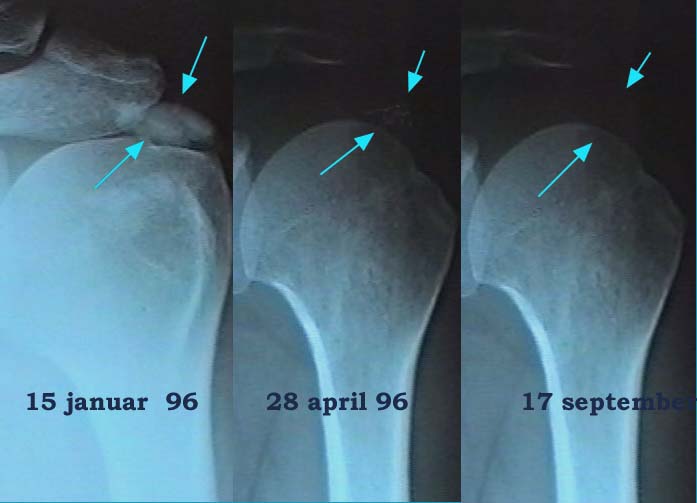

Calcifications

Calcifying tendinitis is a common disorder. Reports on the overall incidence vary between 3 and 7 % of individuals. Most of the calcifications remain symptomless. The supraspinatus tendon is most frequently involved (up to 80% of the cases).

Calcifying tendinitis has a peak incidence in the fifth decade and calcifications are seldom seen in patients older than 70. This means that the 'disorder' is of a self-healing neature and that the various aspects of its pathology are not characteristic of a degenerative disease.

If the tendinitis recurs several times one may conclude that the calcification plays a role in the pathogenesis of the tendinitis and an endeavour must be made to get rid of it.